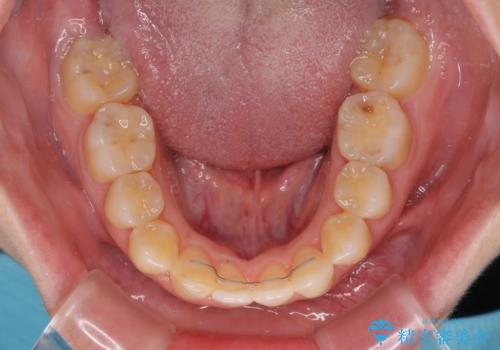

- 学生時代の抜歯矯正の後戻りが気になり、再矯正を希望して来院された患者様です。

マウスピース矯正は継続する自信がなく、気になるところを短期間で改善したいとのことで、ワイヤー装置にて矯正治療を行うこととしました。

詰め物で隠していた下顎前歯の隙間は、歯軸を改善することで詰め物を除去しても隙間が目立たなくなりました。